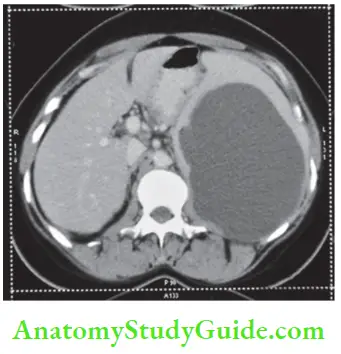

Most of these injuries are diagnosed by CT scan today (CT classification is given).

- CT scan is more reliable. It should be used in cases of doubtful diagnosis and stable patients.1 It also rules out hollow viscus perforation, pancreatic injuries, etc.